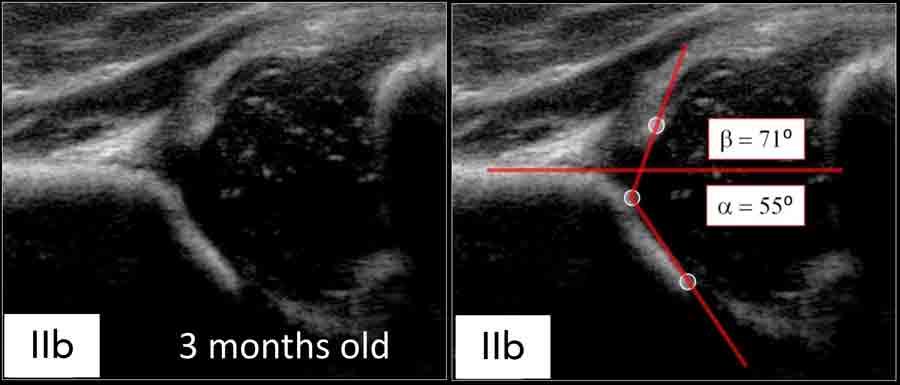

Loại IIb

Nếu trẻ lớn hơn 3 tháng hoặc 13 tuần tuổi, thì góc alpha từ 50-59 độ được coi là dấu hiệu của loạn sản, tức là loại IIb.

Type IIb

Ở độ tuổi 3 tháng hoặc 13 tuần, các phát hiện tương tự dẫn đến kết quả là hông loại IIb.